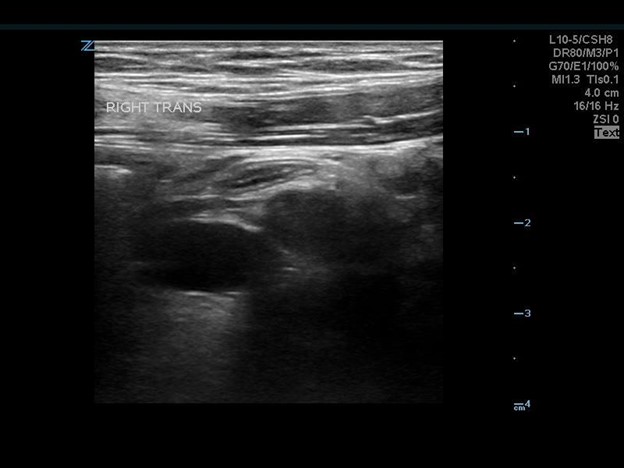

The appendix is most reliably found in the right lower quadrant; the base extends from the proximal cecum and lies anterior to the psoas muscle and the right iliac vessels. Most of the time the distal tip is retrocecal, though the challenge in localization is augmented as the appendix can be pelvically oriented (Images 5 and 6) or directed elsewhere in the abdomen. The normal appendix is tubular, non-peristalsing, compressible, and blind-ended, measuring less than 6 mm. (Image 7)

Image 5. Normal appendix

Image 6. Normal appendix (Yellow: Appendix, Red: Iliac Artery, Blue: Iliac Vein)